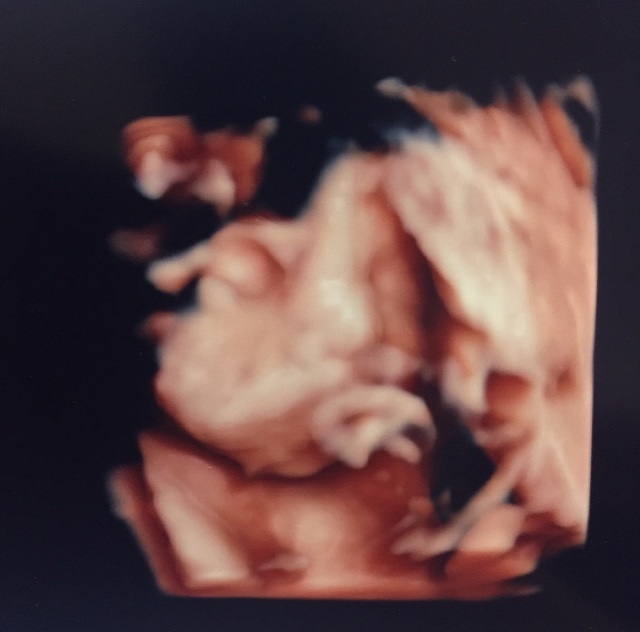

28週0日(28w0d・女の子)|yuzukichi さん(20歳)

エコー写真撮影時のエピソード:

4Dのエコー凄く楽しみにしてました!せっかくの4Dなのに手で顔を隠して寝ていて、なかなか顔を見せてくれず…(泣)

看護師さんがお腹を揺すって頑張ってくれたおかげで顔を見ることができました(笑)エイリアンみたい!って思いつつも見た瞬間キュンってして早く会いたい欲が高まりました!